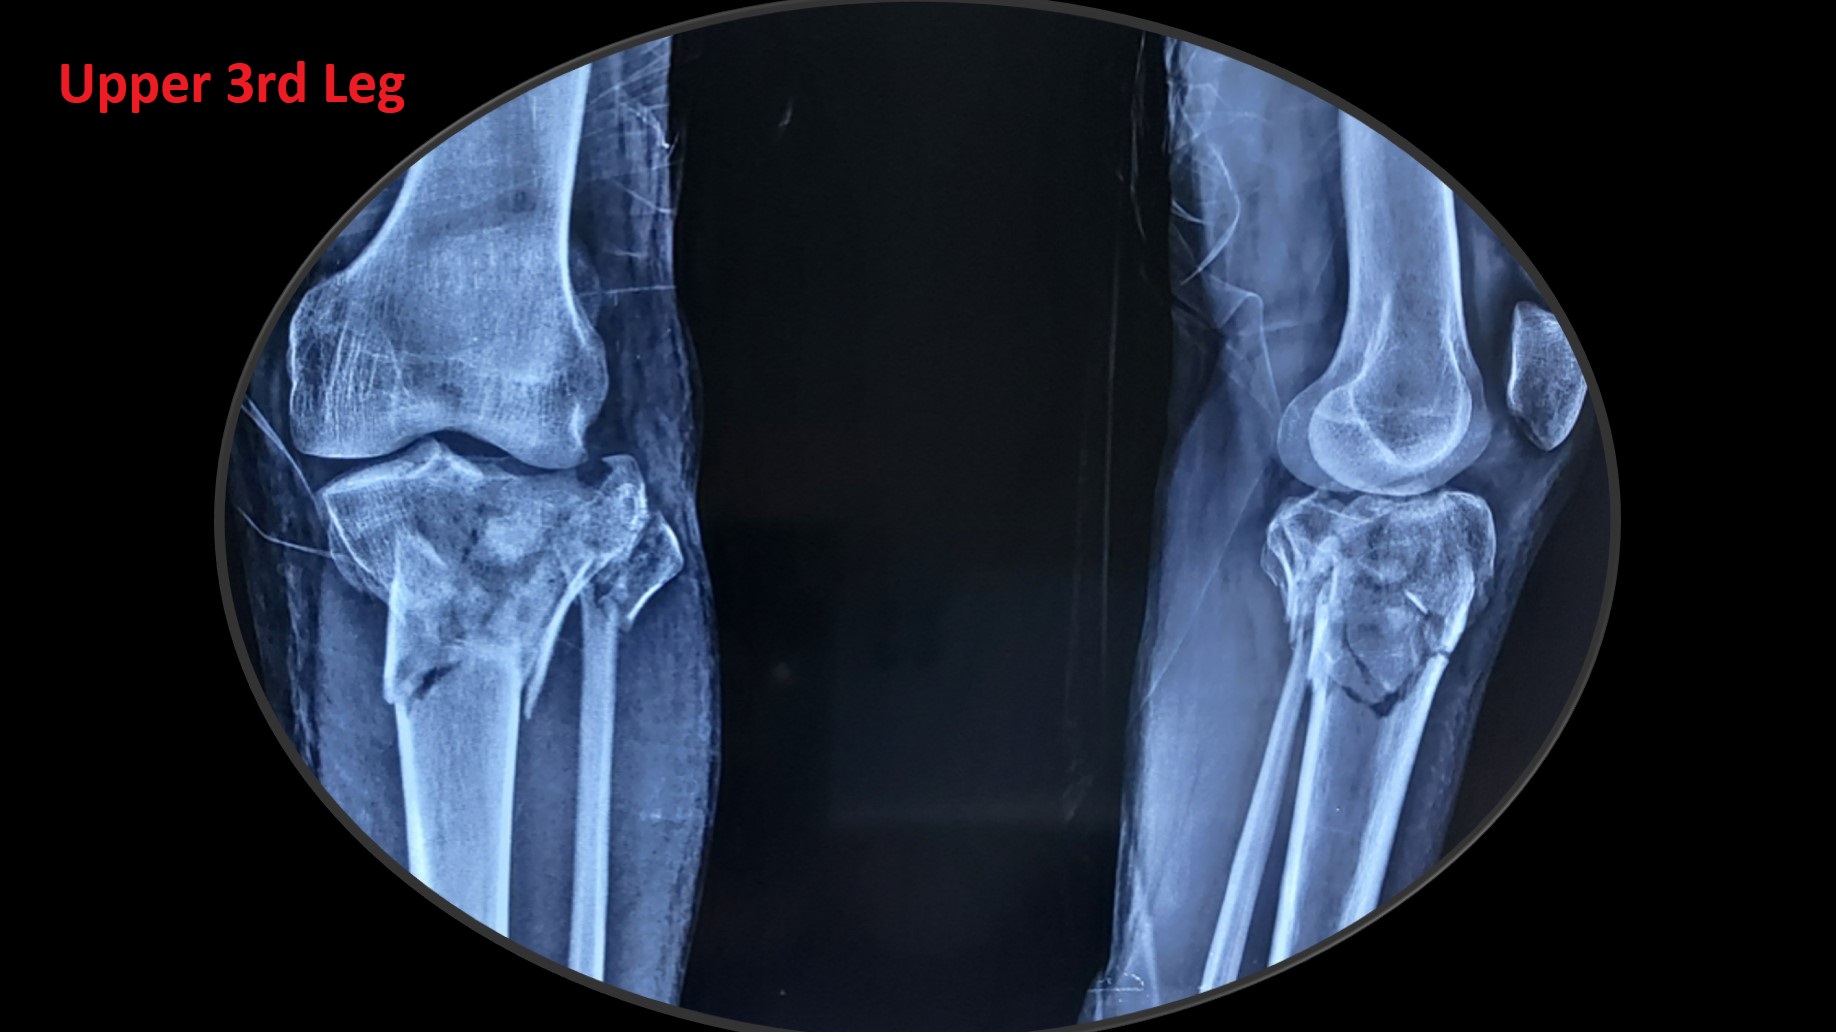

• Most of the metaphyseal fractures of both upper and lower limbs can be successfully treated by CRPP.

• It can be applied to diaphyseal region adjacent to metaphysis in pediatric fractures, especially distal 3rd arm, forearm and leg fractures.

• It can be applied safely in fractures, where ORIF (Open Reduction Internal Fixation ) cannot be performed or postponed due to impending soft tissue complications.